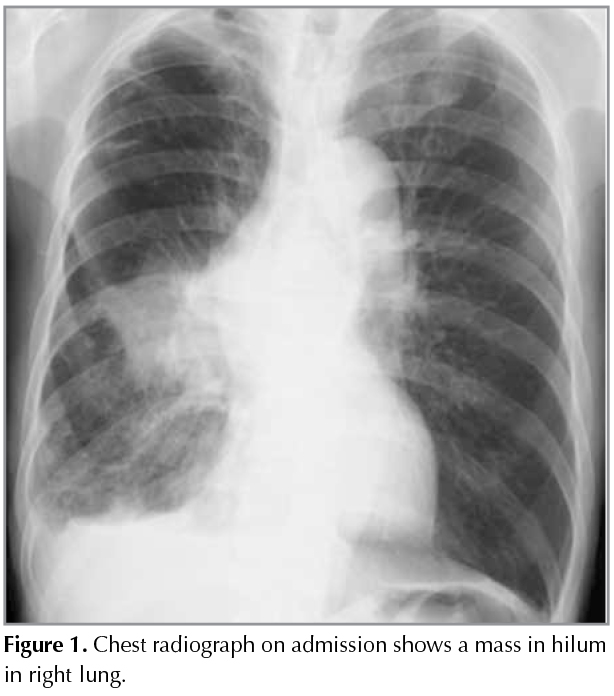

A mass was detected in a 64-year-old man with haemodialysis independent renal impairment undergoing a routine chest X-Ray (Figure 1). Thirteen years ago, the patient had renal biopsy for the correct diagnosis of nephrotic syndrome, and diagnosed as having IgA nephropathy. He treated the disease with prednisolone for ten years. The patient had cough and dyspnea on effort for three months. He smoked one pack-year for 25 years. Chest computed tomography revealed a mass in the right lung with ipsilateral mediastinal lymphadenopathy. There was small amount of pleural fluid in the right hemithorax, which was evaluated as a malignant pleural fluid clinically (Figure 1). Laboratory testing revealed blood ureanitrogen (BUN) 46.0 mg/dL and creatinine (Cre) 2.86 mg/dL. Histopathological analysis obtained by transbronchial biopsy showed squamous cell cancer (Figure 2). A brain computed tomography, abdominal echogram and bone scintigram revealed nodistant metastasis. Due to his impaired renal function, the patient received thoracic irradiation (2 Gy/day, total 50 Gy). He had no additional chemotherapy. On chest radiograph and CT scan three months after the initiation of chest irradiation, volume loss of the right lung due to post-irradiation change was observed, but no apparent finding of recurrence of squamous cell lung cancer was found (Figure 3). During the follow-up period, the patient developed pneumonia twice and herpes zoster in his left back. At these times, his renal function was tentatively deteriorated with BUN 83.0 mg/dL and Cre 5.35 mg/dlL. Fortunately, however, his renal function unexpectedly returned to the revel with BUN 25.0 mg/dL and Cre 2.07 mg/dL 15 months after the thoracic irradiation for the tumor. The patient is now followed up in our outpatient office.